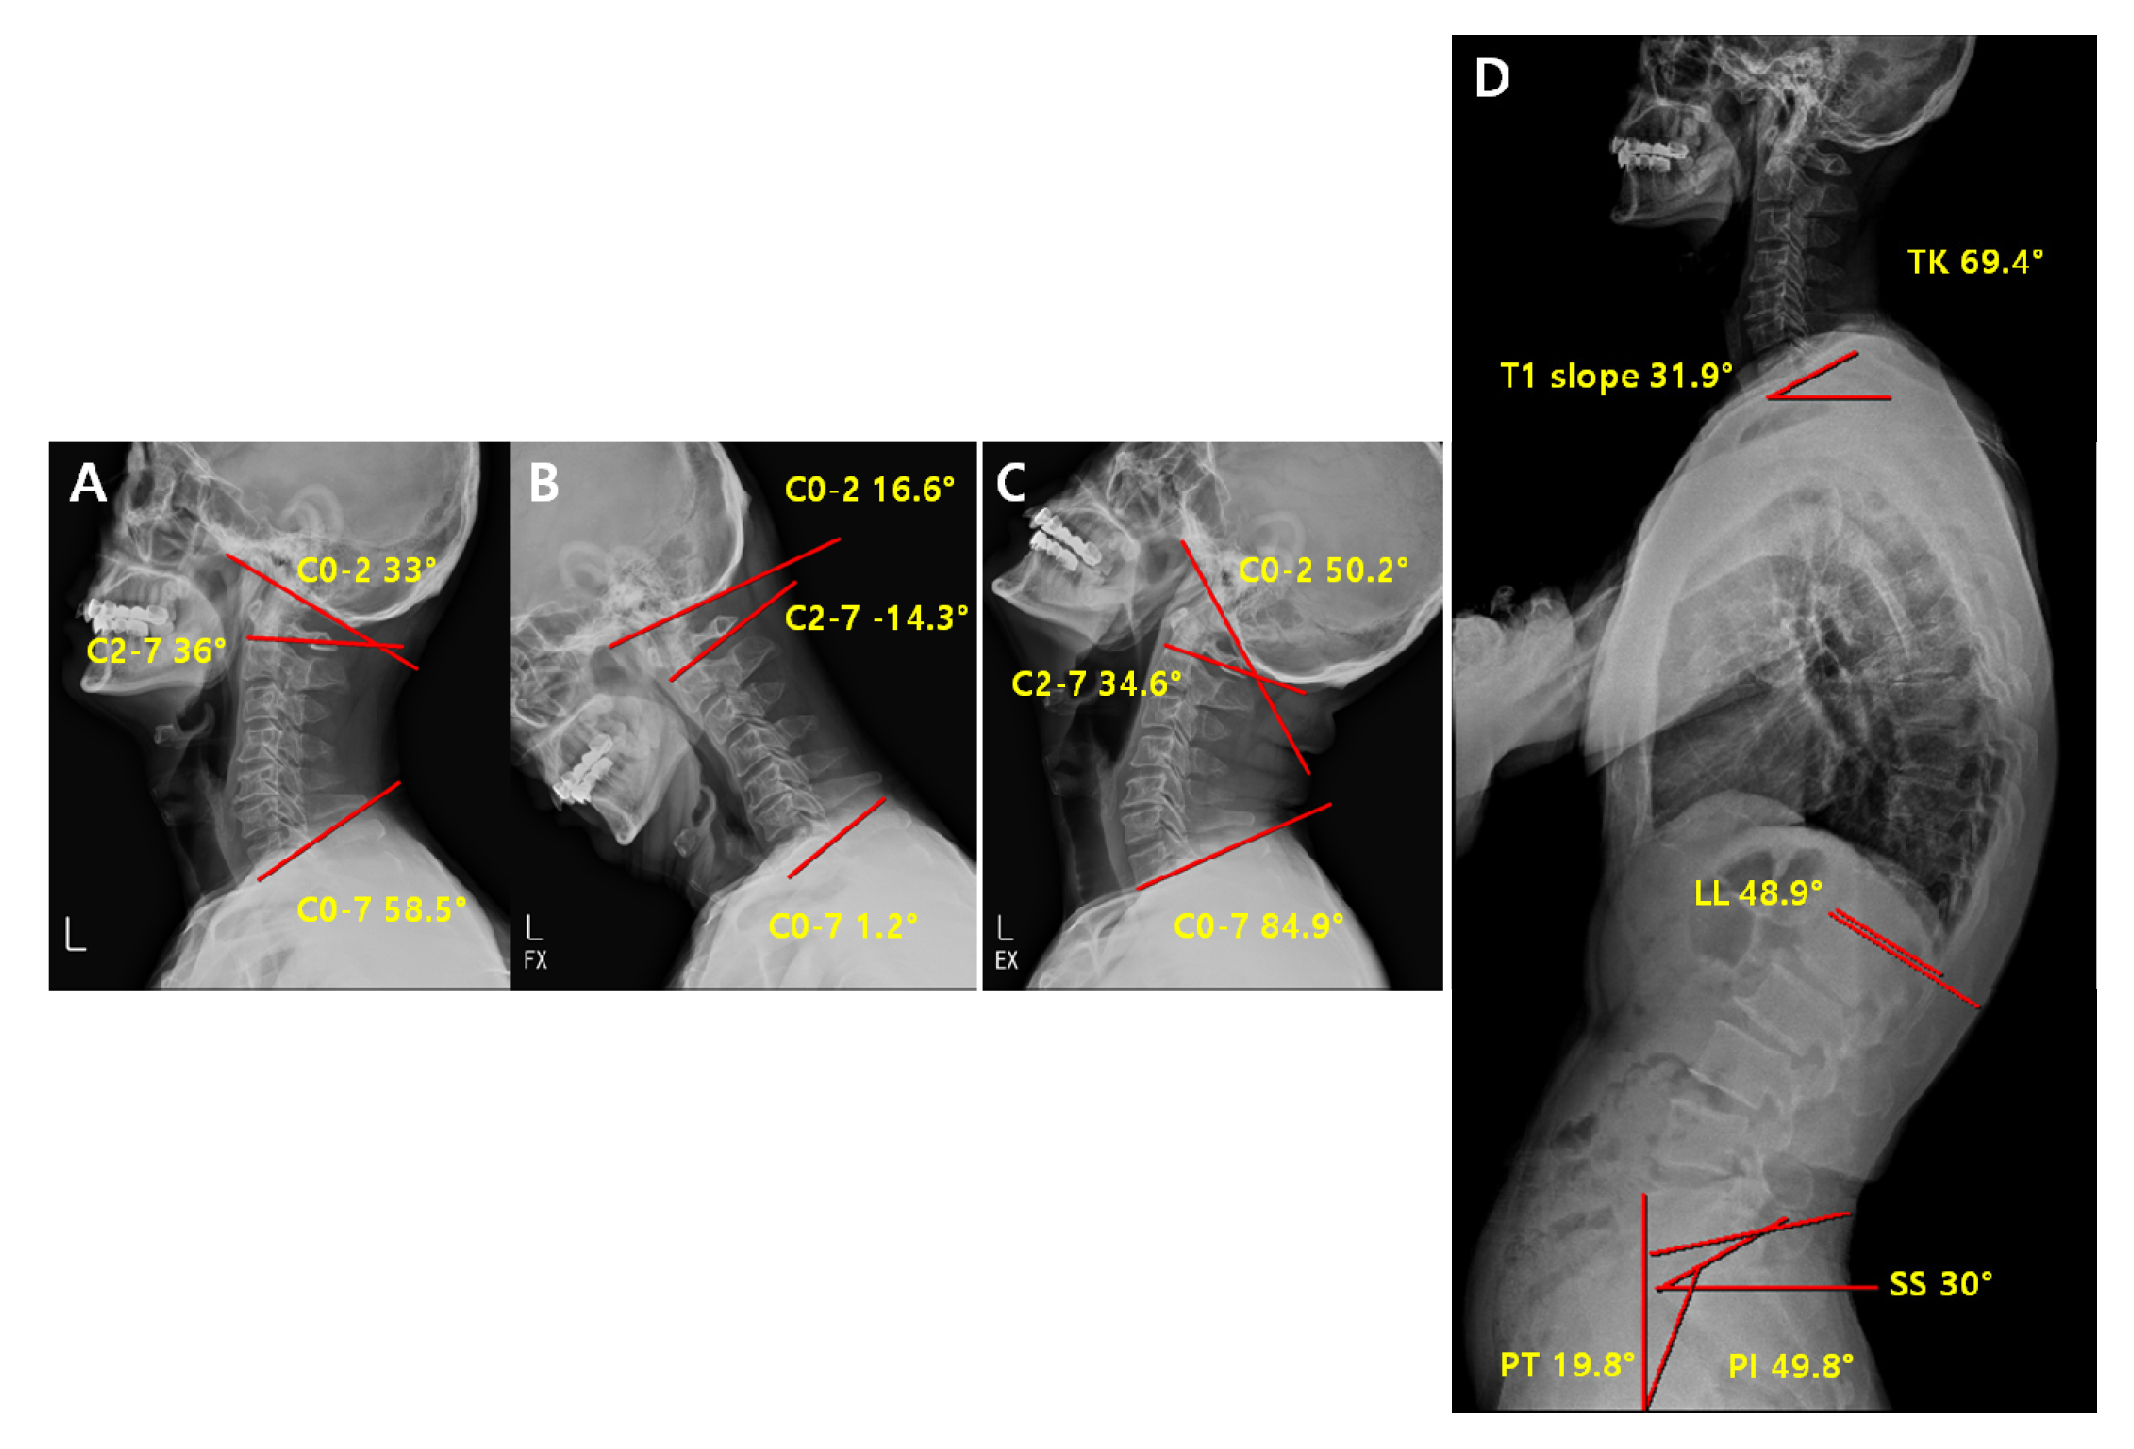

2.3. Radiographic Measurement

2.4. Radiological Analysis